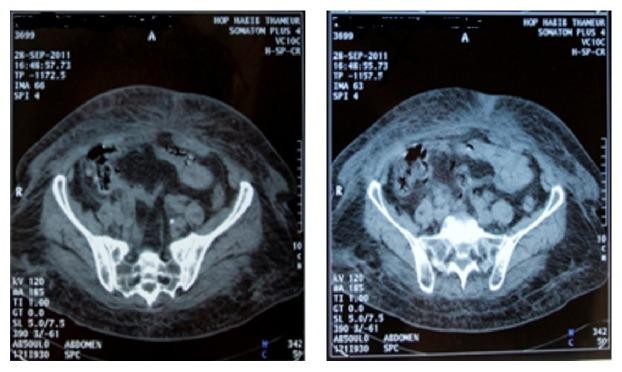

肠壁血肿(MIH)是抗凝治疗罕见的并发症。很少有报道称出血性休克是其首发表现形式。我们报告两例口服抗凝剂治疗主动脉人工瓣膜和心房颤动的患者发生肠壁血肿导致休克的病例。患者因胃肠道出血伴血流动力学不稳定入住重症监护病房。复苏后,腹部CT扫描确诊显示广泛血肿。药物治疗有效,无需手术。口服抗凝剂治疗的患者出现与休克相关的胃肠道出血应提醒医生排查可能的肠壁血肿。紧急诊断和适当的药物治疗可避免手术干预。

https://cdn.ncbi.nlm.nih.gov/pmc/blobs/0231/5337317/f050dca56497/CRIGM2017-5424631.002.jpg

https://cdn.ncbi.nlm.nih.gov/pmc/blobs/0231/5337317/751ff8878530/CRIGM2017-5424631.001.jpg